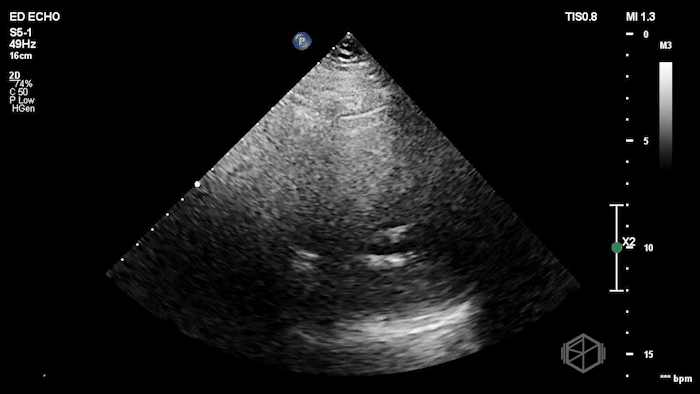

Here is the POCUS:

The POCUS shows a probably borderline LV systolic function. There is significant mitral valve calcification present. There is a mobile echodensity present near the mitral valve. On the color doppler there is severe mitral regurgitation.

In the ED, markedly elevated troponin (~42,000) and BNP 1520. Cardiology TTE revealed a 1.4 × 0.7 cm mobile echodensity on the mitral valve, concerning for papillary muscle or chordal rupture, with differential also including flail leaflet vs. vegetation, in the setting of wall motion abnormalities. The patient had a cath that showed severe triple-vessel CAD, prompting IABP placement and ICU admission. TEE confirmed severe MR due to chordal rupture with preserved LV function. She eventually did get a mitral valve replacement, but had a complex course and ultimately was made comfort care.

Diagnosis: Chordal rupture, acute severe mitral regurgitation